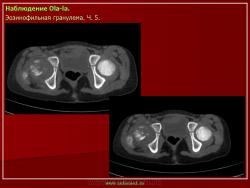

Тело позвонка является наиболее часто поражающейся частью позвоночника. Ранние поражения проявляются, как литические очаги.

Формируется «VERTEBRA PLANA», что может привести к боли и значительным неврологическим расстройствам.